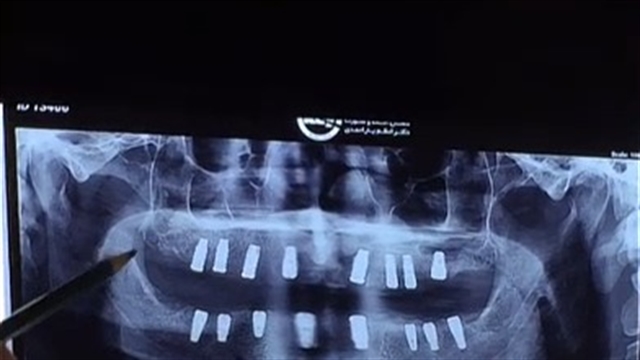

توضیح گرافی کاشت 16 واحد ایمپلنت دندان در یک جلسه همزمان به همراه پیوند استخوان و سینوس لیفت توسط دکتر شهرام اسعدی، متخصص ایمپلنت دندان و جراحی لثه و دارای برد تخصصی فلوشیپ لیزر از گنوا ایتالیا.